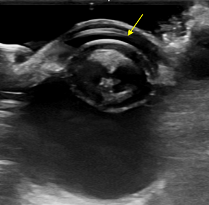

​정확한 진단을 위해 세극등검사 및 안구초음파 검사를 진행하였습니다. 이를 통해 수정체 탈구 증상과, 성숙단계의 백내장을 진단하였습니다.

초음파 검사로 추가 확인

안구초음파 사진에서 수정체가 탈구되어 각막과 거의 맞닿아 있는 사진 / 출처: 에스동물메디컬센터